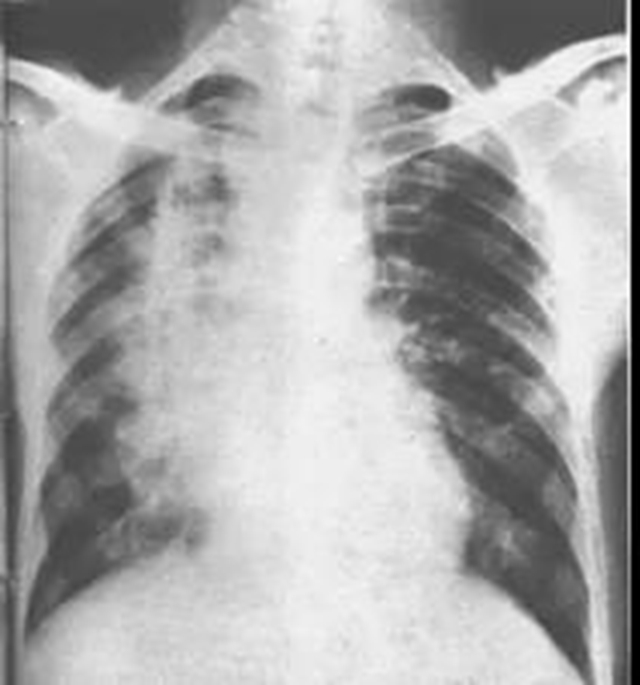

2、急性放射性肺损伤

患者因个体差异、基础疾病(患有慢性肺病)、其他治疗(化疗药物)、吸烟等可能发生急性放射性肺损伤。

目前,临床可使用足量肾上腺皮质激素和抗菌素连续数周(2-3周,甚至1月)进行治疗。